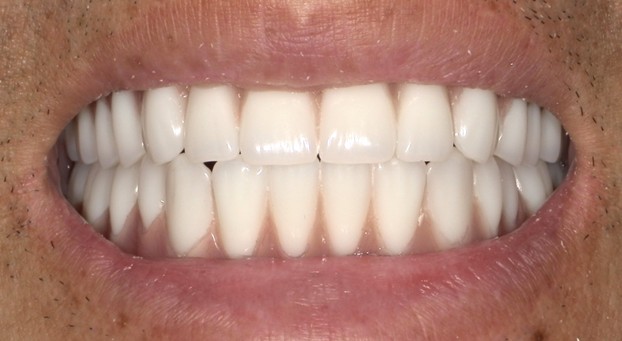

インプラント治療を行った歯は、自然な見た目が特徴です。入れ歯などとは異なり、周囲に気づかれる心配はほとんどありません。